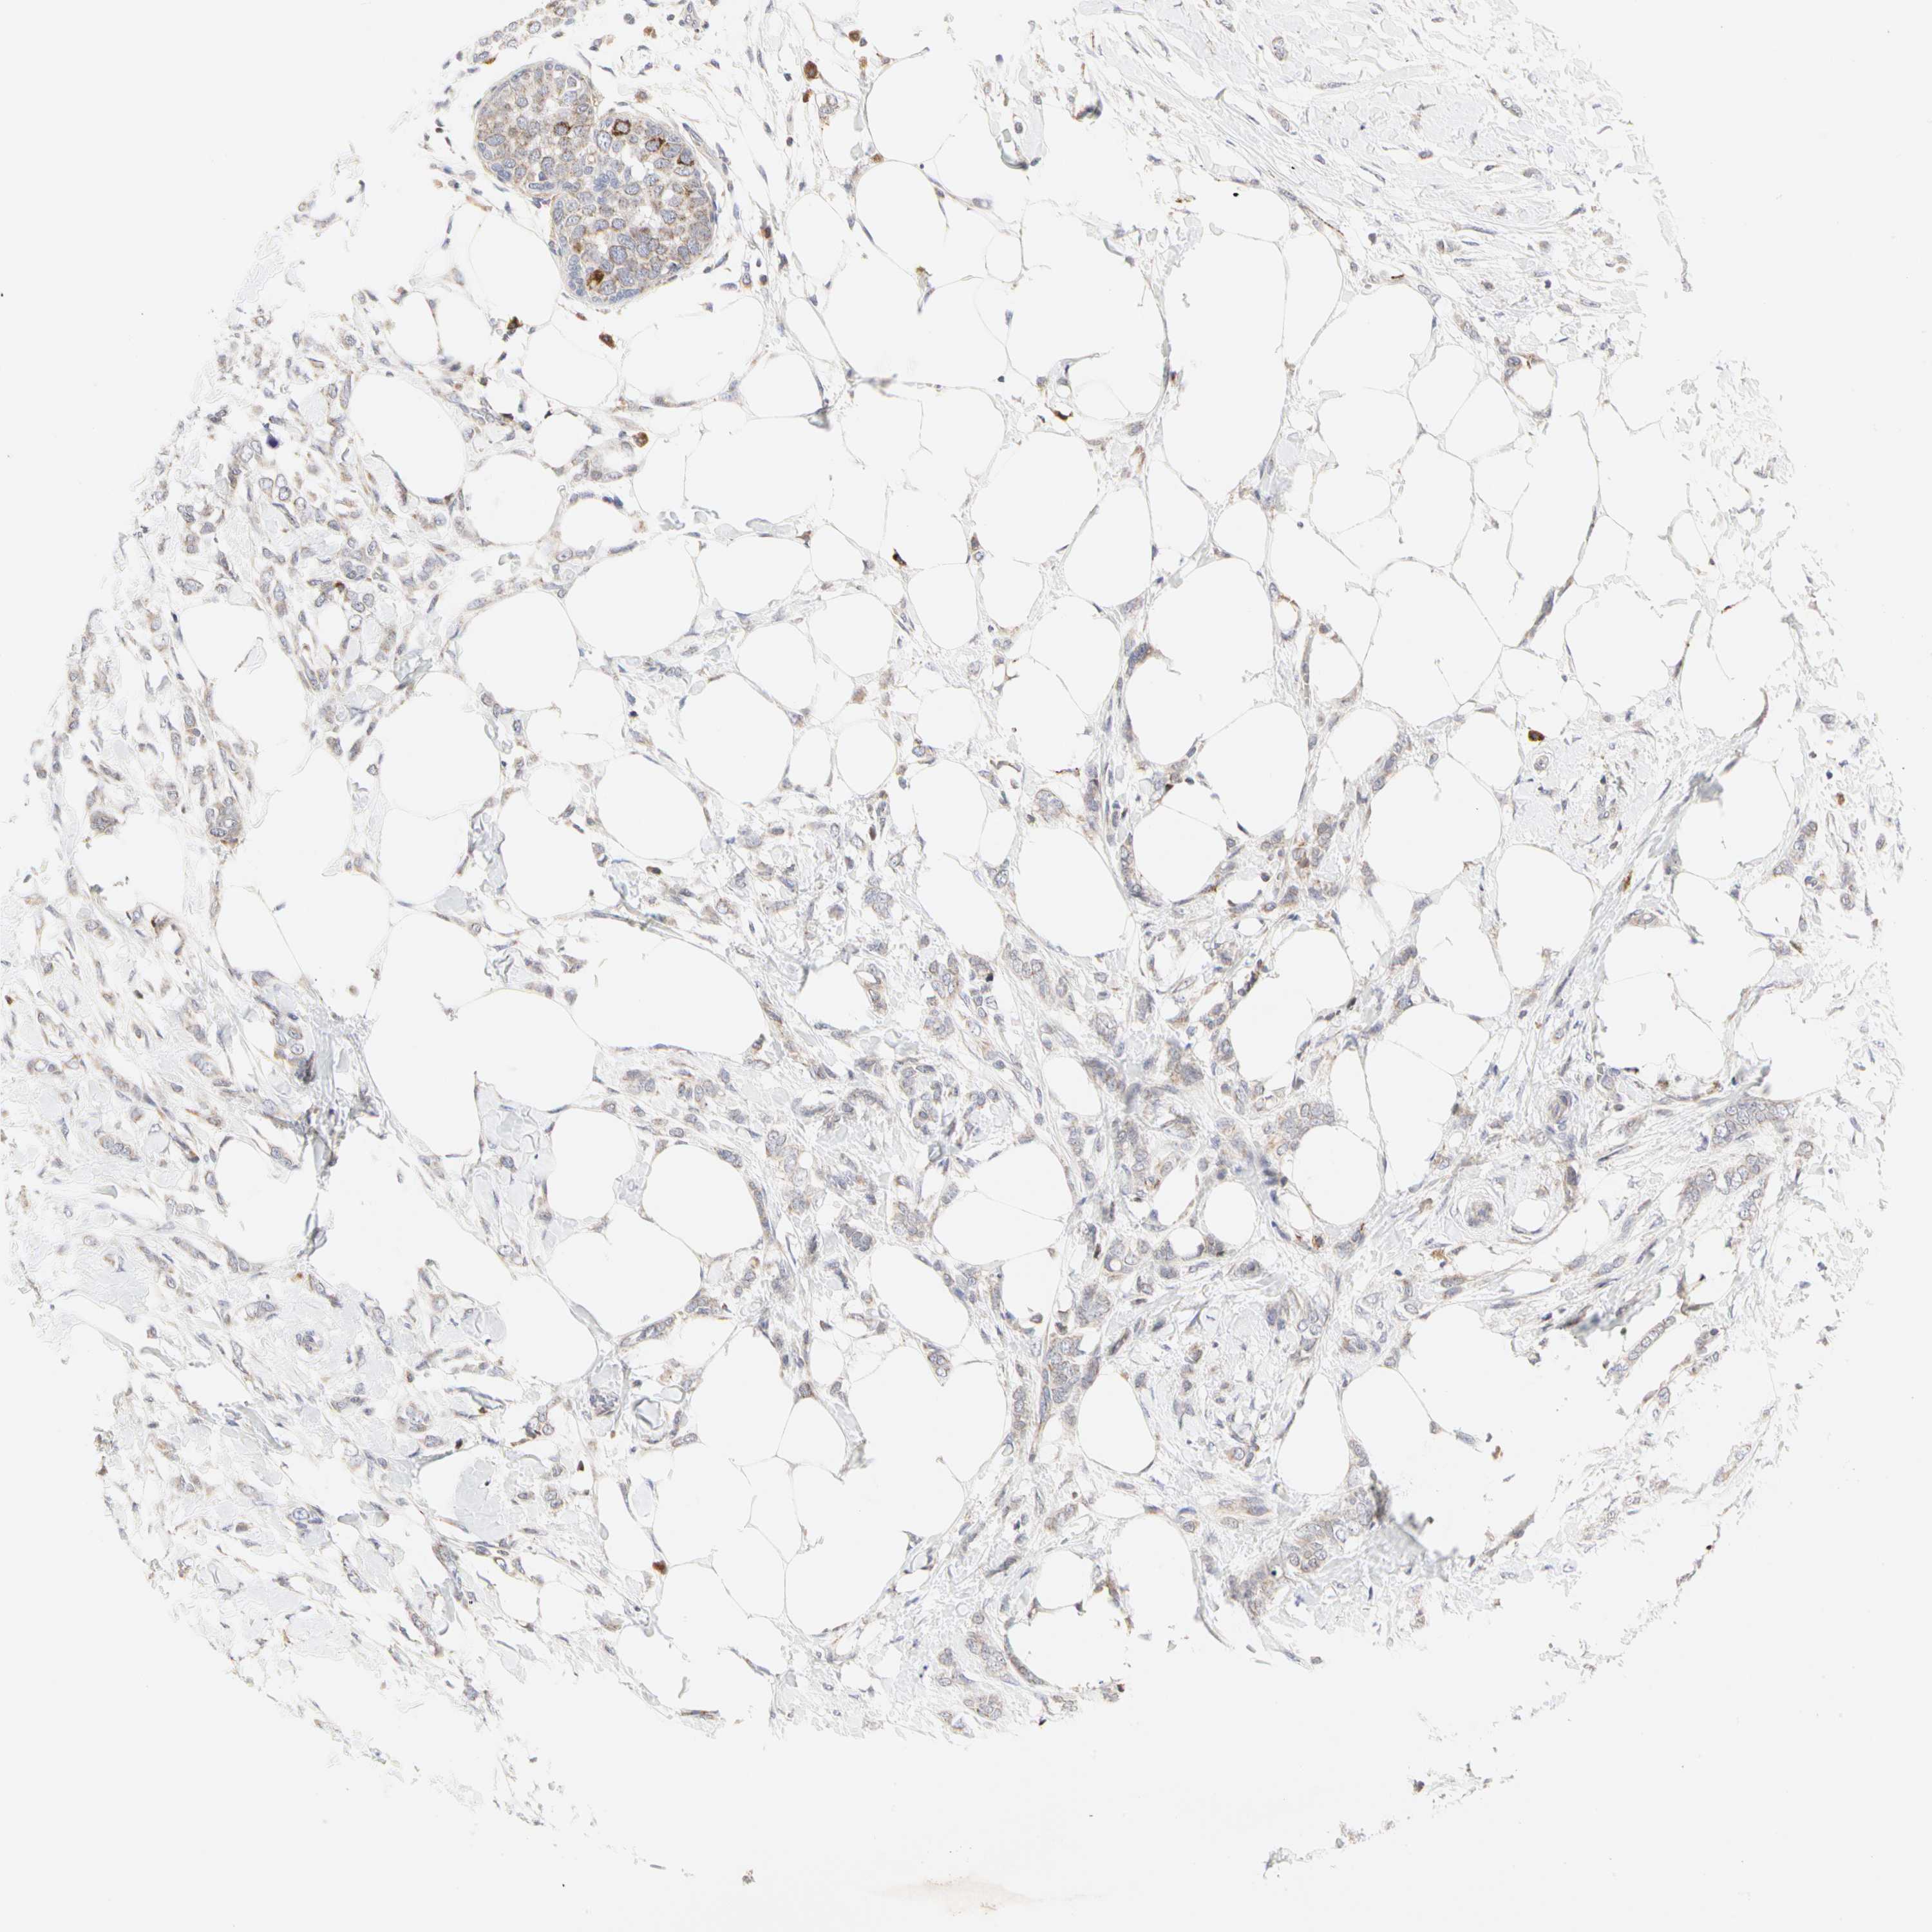

CANCER BREAST CANCER Show tissue menu

BRCA TCGA BRCA VALIDATION PROTEIN EXPRESSION

Breast cancer

Human cancer